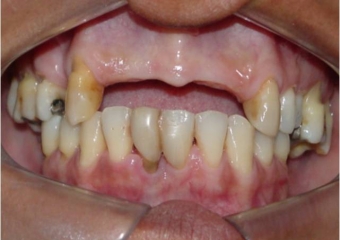

Imagem inicial

Sorriso inicial